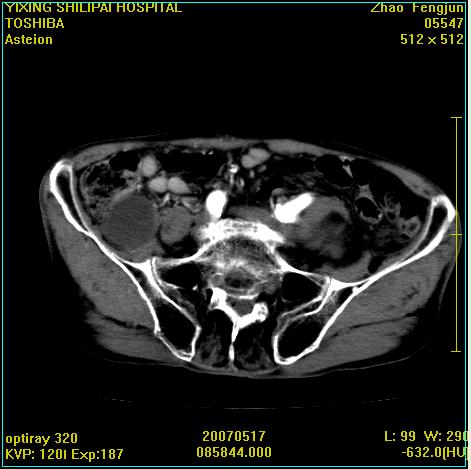

考虑:1、左侧腰大肌囊实性占位性病变(囊性神经根鞘瘤?);

2、右侧兰尾区囊性占位性病变(兰尾囊肿?囊腺癌?类癌?)

以下是引用xiaoniu在2007-5-26 10:45:00的发言:[br]腰大肌的病变应该没有问题,增强扫描还有轻度强化及细小血管影入内,应该排除脓肿,考虑占位性病变,腰大肌的占位多考虑:神经源性肿瘤。另外腹主动脉下端有真假腔的强化,考虑:主动脉夹层。[br][br][本贴已被 xiaoniu 于 2007-5-26 10:46:39 修改过]

以下是引用老爱克斯新网客在2007-5-26 18:26:00的发言:[br]1左下腹囊实性占位肿块,增强后不均匀强化,位于脊柱旁,椎体骨质无破坏软组织无肿胀,考虑神经源肿瘤神经鞘瘤可能大,2右下腹囊性占位性病变,增强后囊壁强化,考虑阑尾囊肿或囊腺瘤,